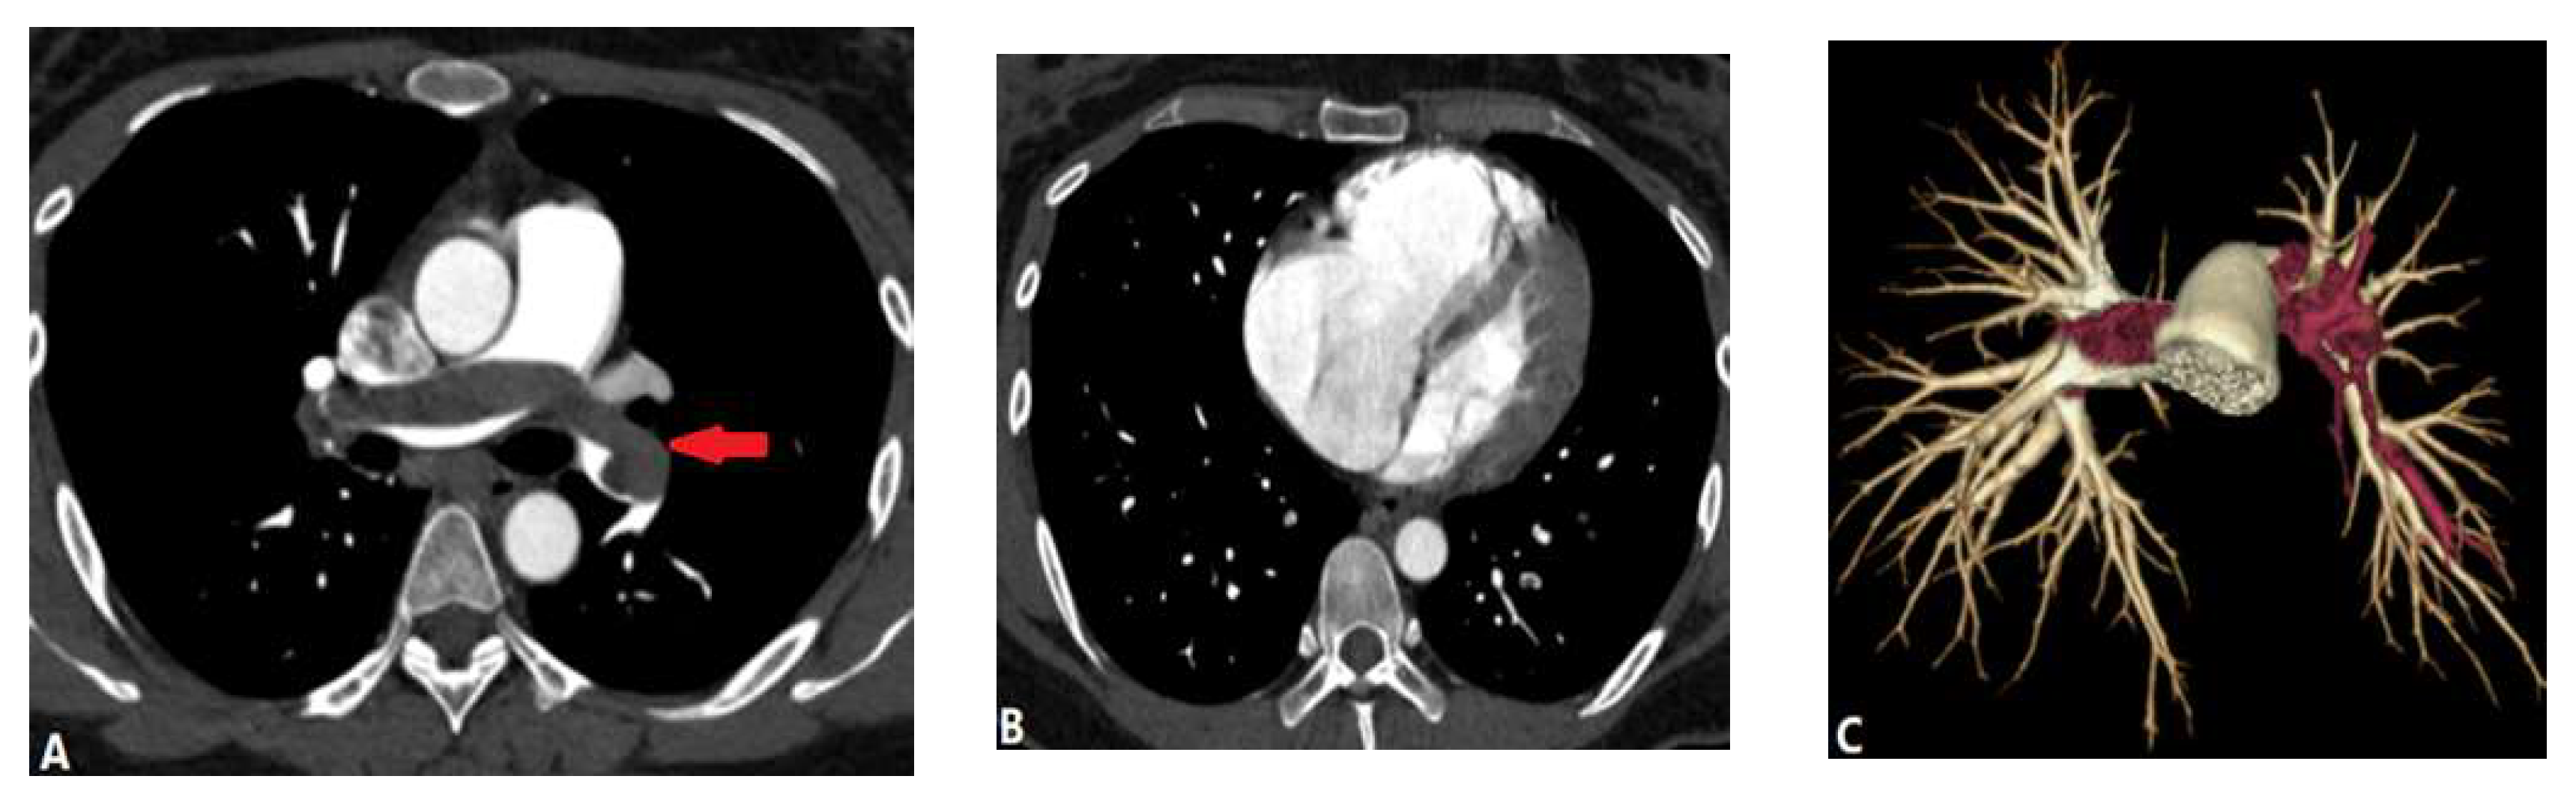

3.2.2. Arterial Dissection (AD)

3.3. Extraluminal Abnormalities